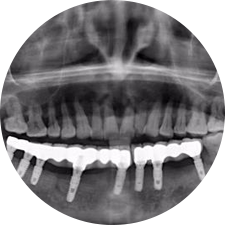

口腔種植是將人工牙根通過手術(shù)植入牙骨內(nèi),獲得牙槽骨牢固的支持,通過特殊的裝置和方式連接牙修復(fù)體,獲得與天然牙功能、結(jié)構(gòu)以及美觀相似的效果。

河北惟德口腔醫(yī)院擁有國內(nèi)豐富的半口/全口、即刻負(fù)重種植案例,十八年案例跟蹤分析,總結(jié)梳理出的各種不同類型的種植案例,Nobel種植體系針對半口/全口缺牙患者,通過4-8顆種植體可快速達(dá)到牙齒重建,不僅植入種植體較少,節(jié)省費(fèi)用,手術(shù)時(shí)間更短。

術(shù)前患者CBCT口掃1:1三維重建,模擬手術(shù)過程及預(yù)測術(shù)后治療效果,確定每顆植體植入的適合的種植位點(diǎn)、深度及角度,有效避免損傷頜骨重要解剖結(jié)構(gòu),提高手術(shù)準(zhǔn)確度與安全性。

Noble口腔種植體系基本不受年齡限制,適用于缺牙修復(fù),也適用于牙槽骨萎縮、骨質(zhì)疏松、高血壓、糖尿病、超高齡的患者,即種即用,只需少量微小種植體,便可輕松微痛快速重建全口咬合,特殊力學(xué)設(shè)計(jì),針對許多年紀(jì)較大,骨質(zhì)條件差,身體耐受力差的缺牙老人也能完成“即種即用”,受到廣泛好評。

惟德口腔種植體系是以患者感受為中心,取代傳統(tǒng)種植牙手術(shù)需要翻瓣、打孔、縫合,術(shù)前、術(shù)中、術(shù)后的繁復(fù)流程,采用3D導(dǎo)航微創(chuàng)準(zhǔn)確種植技術(shù),通過數(shù)字化CAD/CAM掃描技術(shù)獲得缺牙患者口腔數(shù)據(jù),以數(shù)據(jù)為基礎(chǔ)重建口腔模型進(jìn)行模擬種植。

術(shù)前將患者口內(nèi)的CBCT數(shù)據(jù)及咬合關(guān)系上傳到計(jì)算機(jī)中,建立1:1三維重建,模擬手術(shù)過程及預(yù)測術(shù)后治療效果,找出較佳種植位點(diǎn)、深度及角度,獲取實(shí)際種植體在頜骨內(nèi)的具體三維位置,有效避免損傷頜骨重要解剖結(jié)構(gòu),大大降低手術(shù)風(fēng)險(xiǎn),提升種植成功率。